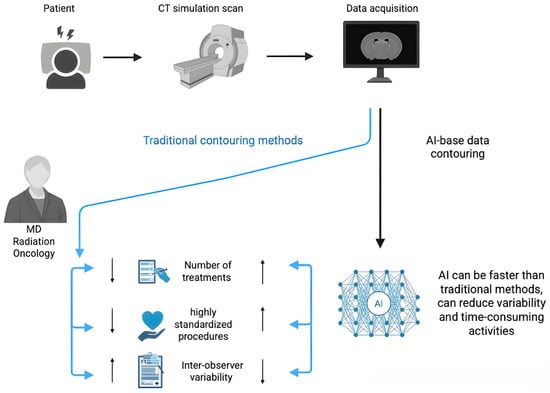

Open AccessArticle

Can Deep Learning-Based Auto-Contouring Software Achieve Accurate Pelvic Volume Delineation in Volumetric Image-Guided Radiotherapy for Prostate Cancer? A Preliminary Multicentric Analysis

by

Cristiano Grossi, Fernando Munoz, Ilaria Bonavero, Eulalie Joelle Tondji Ngassam, Elisabetta Garibaldi, Claudia Airaldi, Elena Celia, Daniela Nassisi, Andrea Brignoli, Elisabetta Trino, Lavinia Bianco, Silvia Leardi, Diego Bongiovanni, Chiara Valero and Maria Grazia Ruo Redda

Curr. Oncol. 2025, 32(6), 321; https://doi.org/10.3390/curroncol32060321 - 30 May 2025

Background: Radiotherapy (RT) is a mainstay treatment for prostate cancer (PC). Accurate delineation of organs at risk (OARs) is crucial for optimizing the therapeutic window by minimizing side effects. Manual segmentation is time-consuming and prone to inter-operator variability. This study investigates the performance

[...] Read more.

Background: Radiotherapy (RT) is a mainstay treatment for prostate cancer (PC). Accurate delineation of organs at risk (OARs) is crucial for optimizing the therapeutic window by minimizing side effects. Manual segmentation is time-consuming and prone to inter-operator variability. This study investigates the performance of Limbus® Contour® (LC), a deep learning-based auto-contouring software, in delineating pelvic structures in PC patients. Methods: We evaluated LC’s performance on key structures (bowel bag, bladder, rectum, sigmoid colon, and pelvic lymph nodes) in 52 patients. We compared auto-contoured structures with those manually delineated by radiation oncologists using different metrics. Results: LC achieved good agreement for the bladder (median Dice: 0.95) and rectum (median Dice: 0.83). However, limitations were observed for the bowel bag (median Dice: 0.64) and sigmoid colon (median Dice: 0.6), with inclusion of irrelevant structures. While the median Dice for pelvic lymph nodes was acceptable (0.73), the software lacked sub-regional differentiation, limiting its applicability in certain other oncologic settings. Conclusions: LC shows promise for automating OAR delineation in prostate radiotherapy, particularly for the bladder and rectum. Improvements are needed for bowel bag, sigmoid colon, and lymph node sub-regionalization. Further validation with a broader and larger patient cohort is recommended to assess generalizability.

Full article

(This article belongs to the Special Issue Evolution of Treatments of Prostate Cancer: From Biology to Current Advanced Technologies)